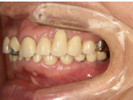

50代女性

![]() |

治療前 |

||

治療中。仮歯。 左上の奥にインプラント埋入。 噛みあわせ治療を行いました |

治療後 全体の歯で食事がおいしくできるようになったと喜んでおられました。 |